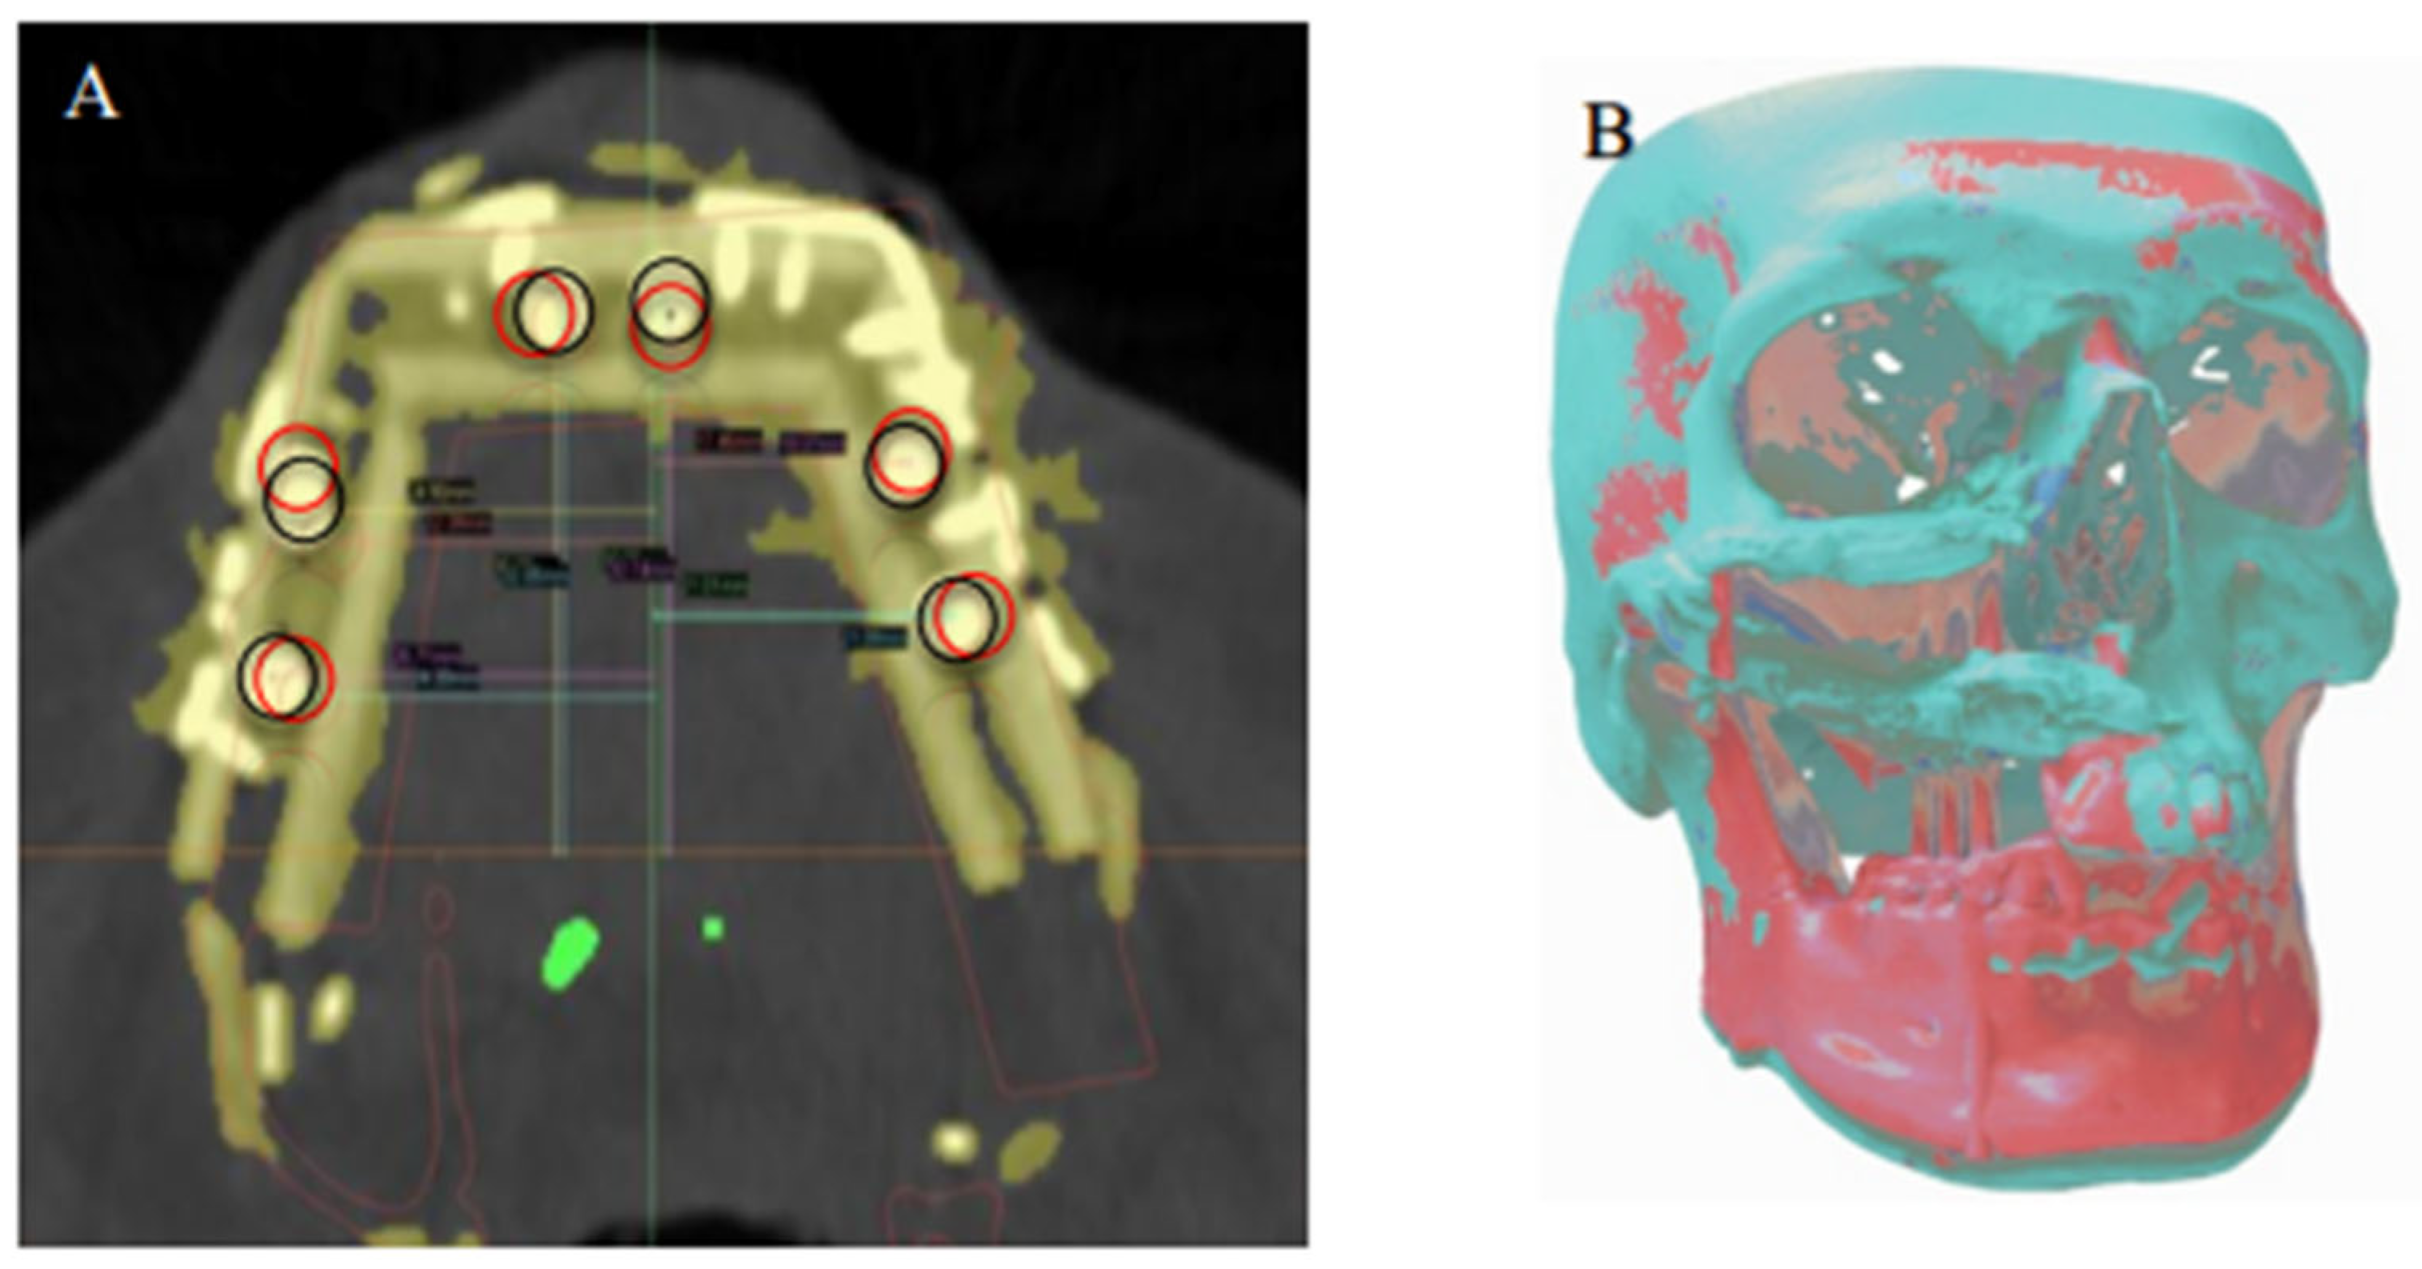

2.6. Data Analysis

The preoperative digital plan, referred to as “planned”, and the scans of the postoperative results, referred to as “actual”, were used for our analysis. Digitally placed spheres (1 mm diameter) were manually positioned in the geometric center of the planned and actual implant positions along the occlusal surface of the fibula. The spheres defined the reference point for measuring implant position. The X, Y, and Z coordinates of each planned and actual implant position were obtained (Figure 5 and Figure 6). The difference in position of the dental implants between the preoperative planned and postoperative actual CT scans was calculated in millimeters.

When the postoperative scans were superimposed on the preoperative SDS plans, the mean center-point distances between the actual and planned implant positions were 1.5 mm (SD ± 1.2 mm) in the X axis, 2.0 mm (SD ± 1.0 mm) in the Y axis, and 1.8 mm (SD ± 1.1 mm) in the Z axis (Figure 7).

Figure 7. (A) Superimposition of the planned (black circles) dental implant locations according to virtual reconstruction planning and actual (red circles) implant locations on the postoperative CT. (B) Registration of the preoperative 3D model and the postoperative 3D reconstruction, showing overall deviation from the virtual plan.